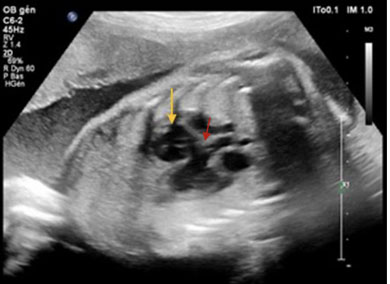

A 63-year-old male presented to the emergency department following a two-week history of a swollen and tender right cheek. The patient had a history of diabetes, with the most recent test performed six weeks prior to the infection showing an A1C of 10.5. The patient also had a history of cirrhosis, and HIV, for which he was being treated with Cabenuva. The patient reported having multiple cosmetic procedures performed in the past, including zygomatic implants, injectable facial fillers, with his last cosmetic procedure being implant replacements following an infection of an unknown organism in 2012. Upon examination, infection was suspected, and the patient was sent for a CT scan as well as a needle aspiration of the right cheek for analysis. The CT scan indicated the presence of a peripherally enhancing organized fluid collection overlying the right zygomatic bone, surrounding the right zygomatic implant measuring about 5 × 1.3 cm axially and 2.3 cm craniocaudally (Figure 1). The fluid collection was surrounded by mild fat stranding as well as mild asymmetric thickening of the overlying skin. The CT scan also showed multiple other hypodense structures located on the left side over the left zygomatic bone (Figure 2), along the inferior margin of the left zygomatic facial implant and lateral to the left maxilla (Figure 3), all favored to represent cosmetic facial fillers. The abscess was surgically drained three days later, and the implant as well as the surrounding fillers were removed. Only the implants and fillers on the affected side were removed as the physician was concerned about the possible risk of spreading the infection. The patient was seen one week later, and no signs of any residual infection were seen, but the patient was still experiencing swelling and discomfort. At this time, the patient was informed that the results from the needle aspiration came back positive for Candida albicans, for which the patient was treated with a two-week course of fluconazole. The patient was seen again in clinic three weeks later and showed no signs of swelling or discomfort following the completion of the 2-week course of fluconazole.

Figure 3: Axial plane CT face with contrast. Infectious collection (dotted arrow) surrounding the right zygomatic implant. Normal appearance of the left zygomatic implant (arrowhead). Small hypodense structures are seen in the subcutaneous soft tissue of the left cheek corresponding to facial fillers.